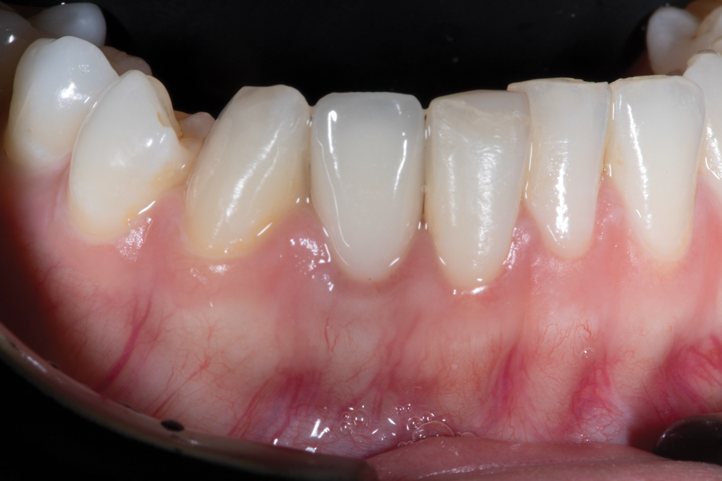

Of note, evaluation of outcome metrics from implant sites performed with socket shields concluded that the socket-shield technique has short-term positive effects related to changes in width and height of buccal bone plate, peri-implant marginal bone levels, esthetic outcomes,76 marginal bone loss reduction, changes in buccal bone width, and higher pink esthetic score (Figure 12 through Figure 14).77-79

Fig 9. Facial view of clinical appearance of facial tissues at 1-year postoperative follow-up.

Figure 9

Fig 10. Oblique view of single-tooth implant No. 8 (1:1) treated with PET. Note the excellent retention of soft-tissue form around the restoration reflecting maintenance of the supporting buccal plate of bone.

Figure 10

Fig 12. Implant placement No. 27 (4:3) after preparation of the root for PET protocol, demonstrating the ability to ideally place the implant within the newly prepared PET socket and maintain the integrity of the surrounding soft tissues.

Figure 12

Fig 14. Final restoration on implant placed into position No. 27 (4:3) with PET protocol, illustrating the final esthetic outcome of this implant and associated restoration in a thin phenotype.

Figure 14